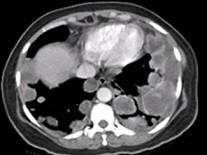

问题 青年女性,咽异物感1年,环状软骨左下方触及一直径2厘米的光滑结节,随吞咽上下活动,生长缓慢,颈部CT检查见下图,患者诊断最可能为 ( )

选项 A、甲状舌骨囊肿 B、颈淋巴结核 C、淋巴结转移癌 D、甲状腺腺廇 E、颈部淋巴瘤

答案 D